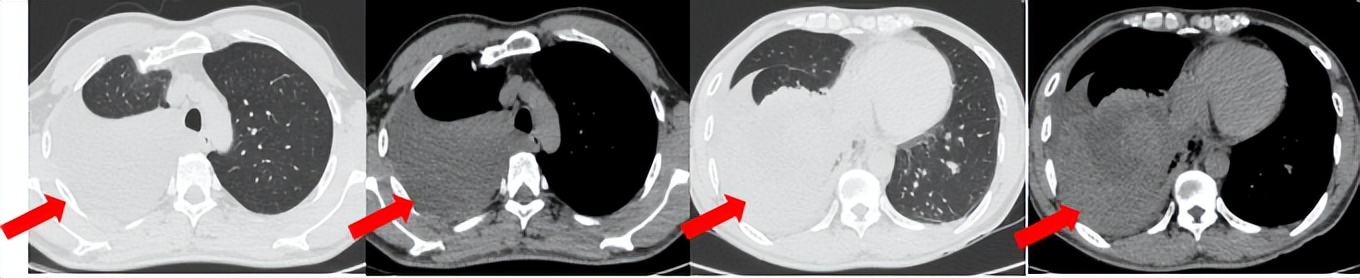

55岁男性,无吸烟史,有饮酒嗜好。2024年11月常规体检胸CT:左肺上叶占位性病变,大小约2.7×2.4cm,恶性可能大;左肺、左侧叶间胸膜及胸膜下多发微小结节,转移待除外。左侧胸腔积液,部分骨质改变。2024年12月初肺穿刺活检,病理:(肺)腺癌。NGS基因检测:CCDC6-RET(exon1-exon12)融合突变阳性(丰度:13.21%)。PD-L1表达阳性(TPS=35%,CPS=45)。

临床诊断:左肺上叶恶性肿瘤cT1cN2bM1a IVA期,肺门继发恶性肿瘤,纵隔继发恶性肿瘤,胸膜继发恶性肿瘤,胸腔积液。

治疗经过:2025.01开始口服普拉替尼(400mg,qd)。2025.03复查胸CT:左肺上叶、右肺上叶、左肺斜裂见多发实性结节影,长径范围约3-17mm,较大者大小约17mm×12mm,位于左肺上叶下舌段,可见分叶、毛刺、胸膜凹陷、棘状突起征象。纵隔内小淋巴结。评效PR,随访中。治疗期间未出现毒性反应。

2024.12

2025.03评效PR